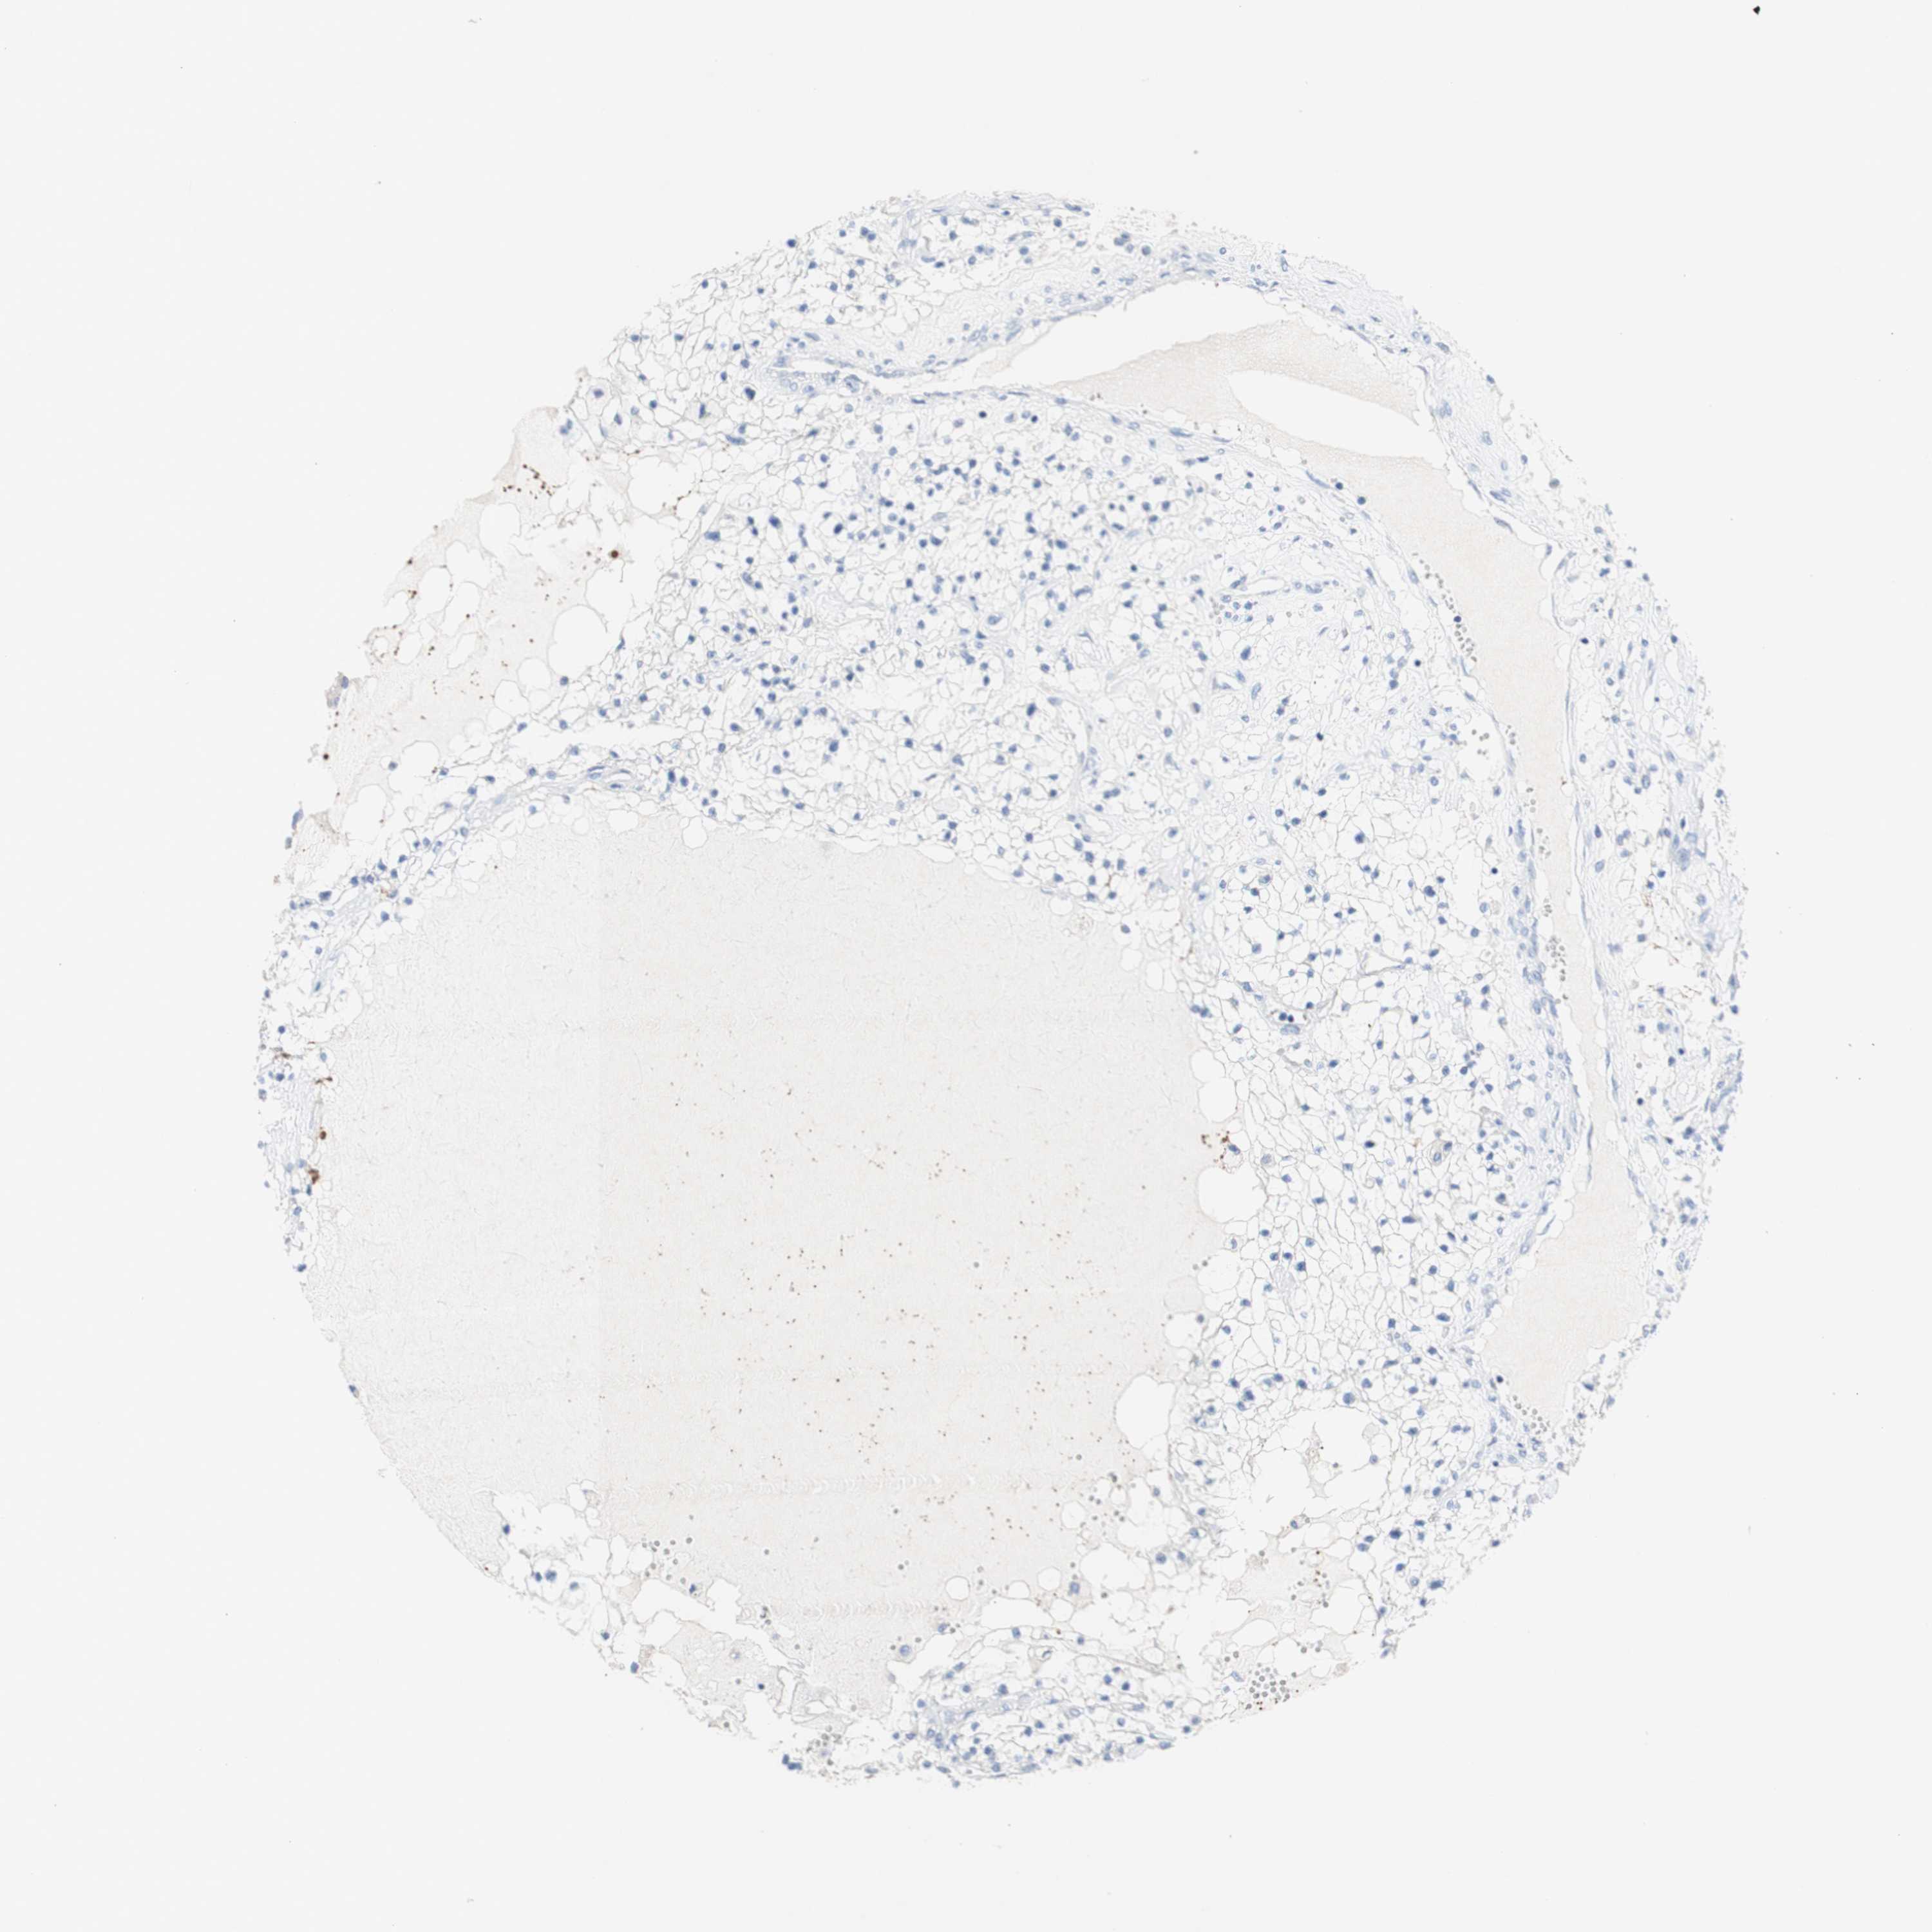

KIDNEY RENAL PAPILLARY CELL CARCINOMA (TCGA) - Interactive survival scatter ploti

The Survival Scatter plot shows the clinical status (i.e. dead or alive) for all individuals in the patient cohort, based on the same data that underlies the corresponding Kaplan-Meier plots. Patients that are alive at last time for follow-up are shown in blue and patients who have died during the study are shown in red.

The x-axis shows the expression levels (FPKM) of the investigated gene in the tumor tissue at the time of diagnosis. The y-axis shows the follow-up time after diagnosis (years). Both axes are complimented with kernel density curves demonstrating the data density over the axes. The top density plot shows the expression levels (FPKM) distribution among dead (red) and alive patients (blue). The right density plot shows the data density of the survived years of dead patients with high and low expression levels respectively, stratified using the cutoff indicated by the vertical dashed line through the Survival Scatter plot. This cutoff is automatically defined based on the FPKM cutoff that minimizes the p-score. The cutoff can be changed by dragging the vertical line or by entering a cutoff value in the square labeled "Current cut-off".

Under the Survival Scatter plot the p-score landscape (black curve; left axis) is shown together with dead median separation (red curve; right axis). Dead median separation is the difference in median mRNA expression between patients who have died with high and low expression, respectively. It is calculated as follows: median FPKM expression of dead patients with high expression - median FPKM expression of dead patients with low expression. This is intended to aid the user in visually exploring custom cutoffs and the associated p-scores and dead median separation.

Individual patient data is displayed and can be filtered by clicking on one or more of the category buttons on the top of the page. Categories describing expression level and patient information include: high, low, alive, dead, female, male and tumor stages. The scale of the x-axis can be toggled between linear and log-scale by clicking on the "x log" button. Mouse-over function shows TCGA ID, patient information and mRNA expression (FPKM) for each patient.

& Survival analysisi

Kaplan-Meier plots summarize results from analysis of correlation between mRNA expression level and patient survival. Patients were divided based on level of expression into one of the two groups "low" (under cut off) or "high" (over cut off). X-axis shows time for survival (years) and y-axis shows the probability of survival, where 1.0 corresponds to 100 percent.

DSC2 is not prognostic in Kidney Renal Papillary Cell Carcinoma (TCGA)